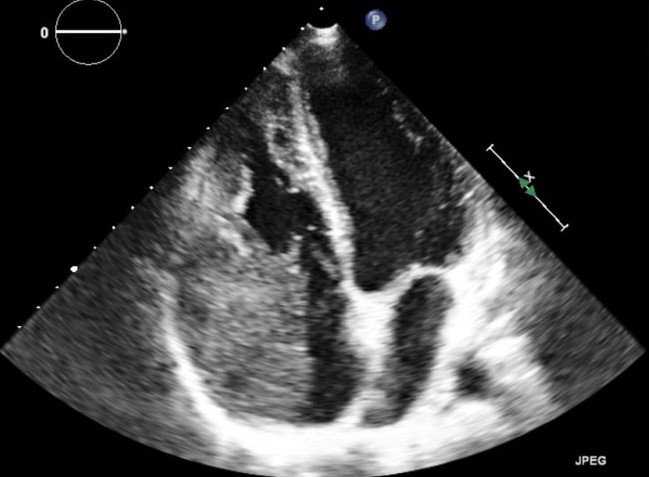

La chemioterapia è consistita in sei cicli di R-CHOP (Rituximab - Ciclofosfamide - Adriamicina - Vincristina - Prednisolone), somministrati in un periodo di sei mesi. Durante il follow-up l’ETT (Figura 12) e la RM cardiaca senza gadolinio (Figura 13) hanno dimostrato una progressiva riduzione della massa fino al 30% della sua dimensione originale, indicando una risposta altamente significativa alla terapia e una buona prognosi.

linfoma_cardiaco_12.jpg

Figura 12

Questo caso clinico, incentrato sul raro riscontro di un linfoma cardiaco primario in un giovane individuo con normale sistema immunitario, esemplifica l'importanza di un approccio d’imaging multimodale al complesso scenario delle masse intracardiache. L’ecocardiografia è una metodica non invasiva e di comune disponibilità per un’iniziale valutazione della sede, della morfologia, delle dimensioni e dell’effetto emodinamico della massa; inoltre essa guida la biopsia intramiocardica e consente il successivo controllo seriale della risposta al trattamento. La tomografia computerizzata è particolarmente utile nel processo di stadiazione, permettendo di valutare la diffusione extracardiaca della neoplasia; risulta inoltre importante nella definizione della malignità del tumore e in una prima definizione della diagnosi differenziale. La risonanza magnetica, sulla base della caratterizzazione tissutale e delle sezioni multiplane per la valutazione dell'infiltrazione cardiaca, fornisce dati essenziali ai fini della diagnosi differenziale. Tuttavia, una diagnosi definitiva si basa sull'analisi istologica.